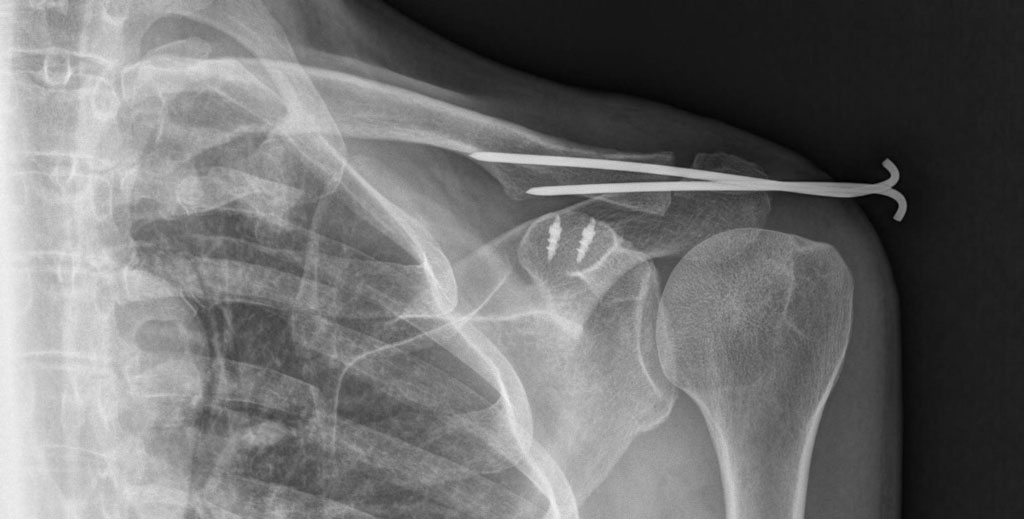

Uma semana depois, eu seria operado no Hospital Santa Catarina, em São Paulo. Os médicos, liderados pelo competente Dr. Fábio Capo, reposicionaram meu acrômio e usaram um conjunto de âncoras e fios metálicos para fixá-lo à clavícula. Também instalaram duas varetas que prenderiam os ossos durante umas seis semanas e seriam, depois, removidas. Eu ficaria dois meses com o braço imobilizado para, então, começar o lento processo de reabilitação.